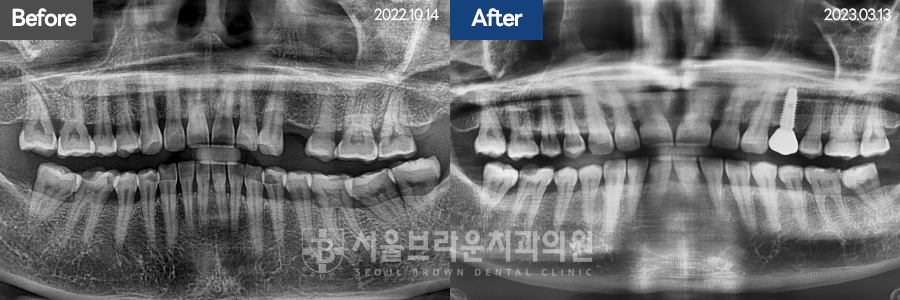

임플란트 | 50대 / 여 / 상악임플란트

50대 / 여 / 상악임플란트